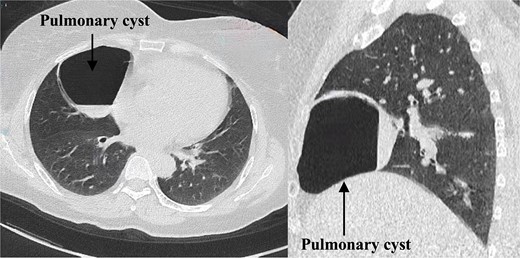

The patient was admitted on 20 March 2024. Enhanced chest CT revealed a solitary cystic lung lesion in the right middle lobe, measuring 8.0 cm × 7.3 cm, with a thin wall and slight compression of the right cardiac border (Fig. 1).

The enhanced scan displayed mild enhancement of the cyst wall without abnormal blood vessels. Pulmonary function tests indicated mild obstructive ventilatory impairment. The patient could ascend 13 floors without stopping during a stair-climbing test. Given the large size of the cyst and a decade of recurrent cough despite conservative treatment, the patient chose surgical intervention. After multidisciplinary consultations, a thoracoscopic right middle lobectomy was planned [7, 8].